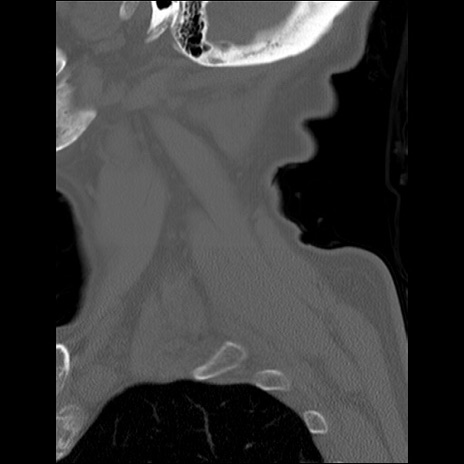

症例48 頚椎CT(矢状断像)

頚椎CT